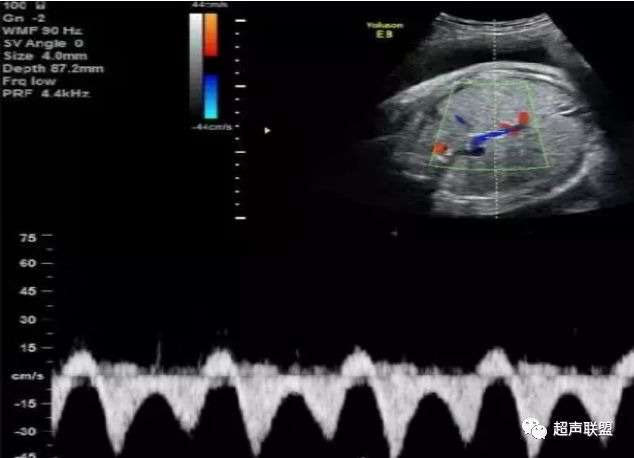

图1 正常脐动脉血流频谱